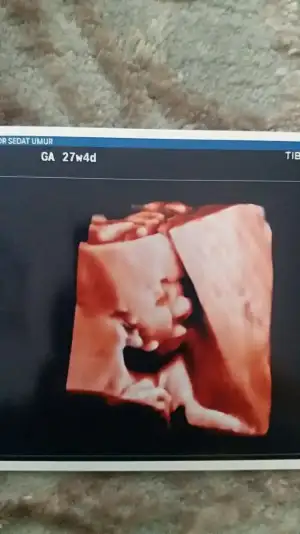

yaa bızım renklı pozlarımza bakın bugune dek bunları aldık 13haftalık biri dha 7cm ordaYok bize de renkli çıktı vermiyo canım. Sadece ekranda renkli görüyoruz ama doğru düzgün bi görüntü değil. O kadar paralar alıyolar bana da çok saçma geldi cihazlarının düzgün görüntü vermemesi. Bi de benim muayene 160 TL operator doktor. Seninki prof falan mı

yaa bızım renklı pozlarımza bakın bugune dek bunları aldık 13haftalık biri dha 7cm orda

Allah'ım ne tatlı özellikle en kucugu çok net çıkmış masallah kuzucuğa.yaa bızım renklı pozlarımza bakın bugune dek bunları aldık 13haftalık biri dha 7cm orda